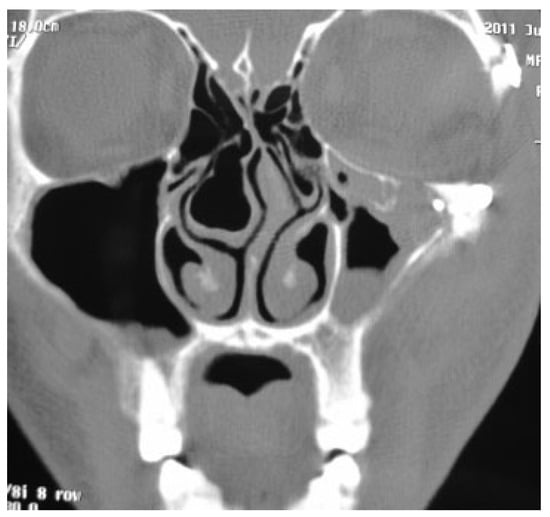

In this prospective study different parameters using biode-gradable plates for reconstruction of the blow-out fractures were assessed. The study was approved by the research committee of the medical ethics group of Shiraz University of Medical Sciences. The study sample was derived from the patients who referred to the Department of Craniomaxillo-facial Surgery for evaluation and management of orbital fracture between January 2009 and December 2010. Patients eligible for study inclusion had an impure blow-out fracture and there was a need to repair orbital floor and to fix the zygomaticomaxillary complex in a proper position. Patients who had pure blow-out fracture or minimal bone displace-ment in computed tomography (CT) scan views without the enophthalmos or the diplopia were excluded from the study. All the patients had a recent trauma and subsequently surgi-cal intervention was made between 1 and 10 days. A consul-tation was made with ophthalmologist before the surgical intervention. An axial and coronal CT scans were taken through 2-mm cuts for each patient before surgical interven-tion, immediate, and 18 months after surgery (Figure 1 and Figure 2). The amount of the orbital floor defect was measured in each case through CT scan. The surgical approach consisted of mid-lower incision for accessing the orbital rim and floor. Bone reduction and reconstruction was made through biode-gradable plate (PG910/PDO) (Figure 3). Titanium miniplates and screws were used for fixation of fractured infraorbital rim. The thickness of the biodegradable plates (PG910/PDO) was 0.5 mm. All the patients underwent secondary interven-tion to remove the titanium miniplates after 18 months. The orbital floor was reevaluated during the secondary interven-tion. The evaluation of remnant defects and biodegradable plates (complete or partial resorption) was made for every patient (Figure 4).

Results demonstrated that 4 out of 15 patients had remnant defects after the resorption of plate. In 10 out of 15 patients biodegradable plates were completely replaced with fibrous tissues after 18 months. In 5 out of 15 patients, partial resorption of plates was observed. There was no relationship between the defect size and the remnant defects (p > 0.05). A significant relationship was seen between the defect size and the plates’ resorption rate (p < 0.001). As a result, when a larger biodegradable plate was used to reconstruct the defect, the plates had partial resorption as compared with the smaller plates that had total resorption after 18 months (Table 2). There is a significant relationship between the resorption rate and the remnant defect. When the plates had incomplete resorption, the risk of the remnant defects to be encountered is increased. Evaluation of the data did not show any correla-tion between patients’ age, remnant defects, and plates’ resorption (p > 0.05). Sex did not have any impact on the defect size, remnant defects, and plates’ resorption (p > 0.05).

Figure 4. Image shows a fibrous layer in the orbital floor 18 months after reconstruction without defect.